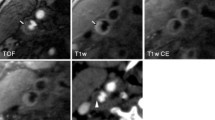

According to the criteria of North American symptomatic carotid endarterectomy trail (NASCET)[10], carotid and cerebrovascular arteries were divided into 40 segments including common carotid artery (CCA), carotid bifurcation (CB), external carotid arteries, internal carotid arteries (ICA) (C1-C7), extracranial vertebral artery (eVA), intracranial vertebral artery (iVA), basilar artery (BA), anterior cerebral artery (A1, A2), middle cerebral artery (M1, M2), posterior cerebral artery (P1, P2), anterior communicating artery (ACoA), and posterior communicating artery (PCoA). These segments were also divided into 3 categories, including extracranial arteries (CCA, CB, CA, C1, and eVA), intracranial ICA (C2-C7), and intracranial arteries(iVA, BA, A1, A2, M1, M2, P1, P2, ACoA, and PCoA). Only segments with a diameter >1.5 mm (as measured on the MDCT angiogram) were included. The type of plaque was determined using the following classification proposed by Ballotta E et al.[11]: 1) non-calcified plaques, plaques having lower density less than 50 HU; 2) calcified plaques, Plaques with a mean attenuation of 130 HU or greater; and 3) mixed plaques, plaques with a mean attenuation of 50-129 HU (Figure 1). A grade of stenosis was assigned for each chosen segment: grade 0 for normal or no observable plaque, grade 1 for diameter stenosis <30%, grade 2 for 30%–69% diameter stenosis, grade 3 for plaques with 70%–99% diameter stenosis, and grade 4 for 100% occlusion (Figure 1)[10]. Finally, it was determined whether the plaque was obstructive or not, using a threshold of 70% luminal narrowing. Each vessel was analyzed on at least two imaging planes, one parallel and one perpendicular to the course of the vessel, and the vessel diameters were measured on perpendicular to the vessel course. For each patient the number of diseased segments, type of plaque and degree of stenosis were determined and recorded.

MDCT identified 183 (93.8%) and 12 (6.2%) patients with and without cerebrovascular disease. A total of 1056 segments with plaque were identified. With regard to plaque constitution, 450 (42.6%) of the plaques were classified as non-calcified plaques, 192 (18.2%) as mixed and 414 (39.2%) as calcified plaques (Figure 2). Among these segments containing plaques, mild stenosis was observed in 562 (53.2%) segments, moderate stenosis in 291 (27.6%) segments, severe stenosis in 170 (16.1%) segments, and occlusion in 33 (3.1%) segments. In general, eight hundred and fifty-three (80.8%) plaques showed non-obstructive and 203 (19.2%) plaques showed obstructive.

There was different degree of stenosis in different plaques. Non-calcified plaques resulted in mild (72.9%), moderate (18.9%), severe stenosis (6.4%) and occlusion (1.8%), mixed plaques resulted in mild (60.4%), moderate (28.6%), severe stenosis (8.9%) and occlusion (2.1%), and calcified plaques resulted in mild (28.5%), moderate (36.5%), severe stenosis (29.9%) and occlusion (5.1%), respectively. As shown in Figure 3, there was a trend that non-calcified plaque resulted in a higher incidence of non-obstructive lumen narrow and calcified plaque resulted in a higher incidence of obstructive lumen narrow. In total, non-calcified, mixed and calcified plaques mainly resulted in non-obstructive lumen narrowing, 91.8%, 89.0% and 65.0% respectively.